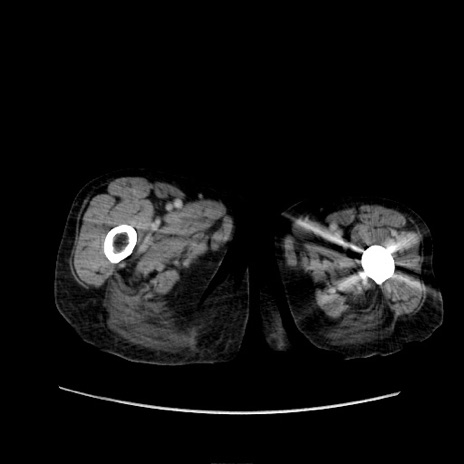

症例31(横断像)

【症例】80歳代 女性

【主訴】腹部膨満感

【現病歴】他院にて肝硬変にてフォロー中。1週間前から便秘、腹部膨満感、臍部腫瘤あり受診となる。

【既往歴】肝硬変

【身体所見】腹部膨隆あり、皮膚変化なし、疼痛なし。

【データ】WBC 4600、CRP 0.25